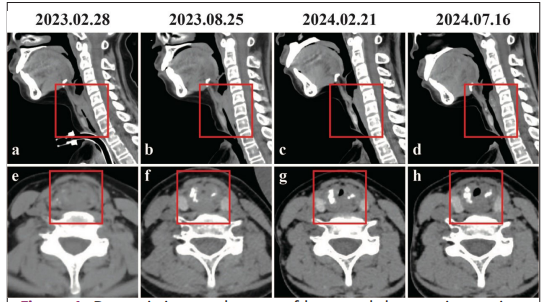

影像下患者气道逐步由闭塞实现开通

在出院后2年的4次就医中,王振刚团队依复查结果,多次调整药物治疗,小云喉部气道的闭塞范围逐渐减小,最终实现再次开通,并能够堵管12小时以上。目前,她已返学一年半,家庭劳动及在校生活基本恢复正常。